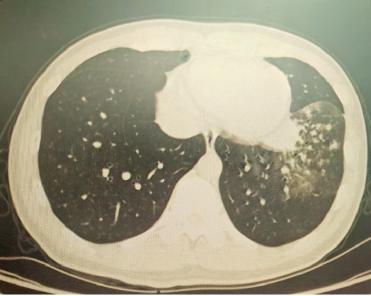

以上是他的胸部CT影像,主要表现为左下肺炎症,片絮影+磨玻璃影。

肺部感染的影像学特征

多发性结节伴快速进展

CT表现为双肺多发实性结节(直径0.5-3cm),结节边缘可见毛刺征及分叶征,特征性表现为短期内体积呈几何级数增长(如1周内增大10倍),需与转移瘤、结核球等鉴别。

混合性密度影与胸腔积液

40%病例出现磨玻璃影与实变影共存,部分结节中央可见液化坏死;30%伴单侧渗出性胸腔积液,积液分析呈渗出性但培养阴性,此表现易误诊为脓胸。